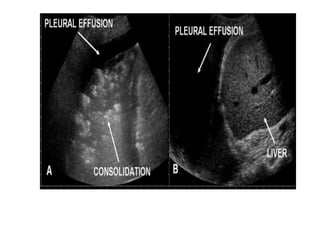

Tissue pattern representative of Alveolar

Consolidation

Presence of hyperechoic punctiform

images

imagesrepresentative of air bronchogramsrepresentative of air bronchograms

Pleural

effusion

Lower lobe

Tissue pattern representativeof Alveolar Consolidation Presence of hyperechoic punctiform images Presence of hyperechoic punctiform imagesrepresentative of air bronchogramsrepresentative of air bronchograms Pleural effusion Lower lobe